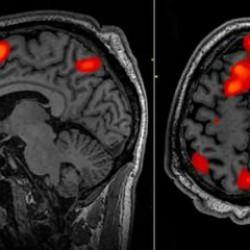

"Türkiye'nin insanlı ilk uzay görevi için eğitim süreci ABD'de başladı. Uzay yolcularımız olası basınç kayıplarına karşı vücutlarını iyi tanımak zorundalar. İşte irtifa eğitimleri sırasında bunu öğreniyorlar!" ifadelerine yer verildi.

Uzay yolcularımız olası basınç kayıplarına karşı vücutlarını iyi tanımak zorundalar.

İşte irtifa eğitimleri sırasında bunu öğreniyorlar!